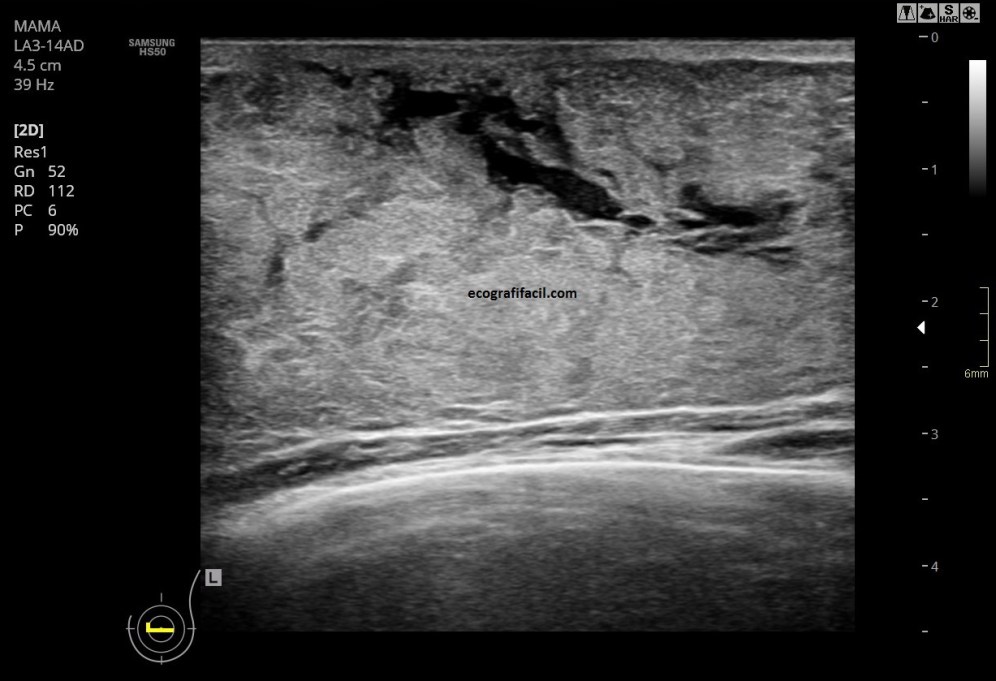

En la figura 1 y 2 vemos una imagen de la región retroareolar, en la imagen 2 ves claramente los conductos dilatados alargados y anecoicos tras del pezón.

In figure 1 and 2 we see an image of the retroareolar region, in image 2 you see clearly the dilated ducts.